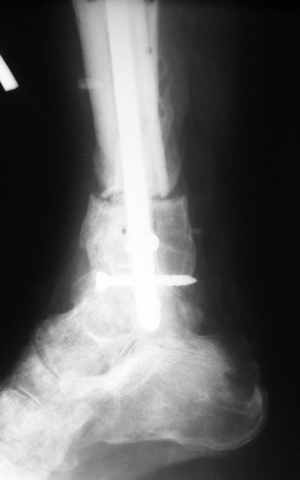

Больному выполнена резекция малоберцовой кости, ВХО раны, сближение отломков. Резекция м\б через отдельный разрез. После ВХО компрессия в аппарате, края раны сближены наводящими швами (без натяжения).

В случае гладкого заживления раны, при условии положительного решения вопроса с металлом, планируем перемонтаж аппарата Илизарова, дополнительную резекцию дистального отломка, выведение полокости голеностопного сустава в правильное положение (см. боковую Р-грамму), одномоментно остеотомия большеберцовой кости. После восстановления длинны голени, по всей видимости, артродез голеностопного сустава.

Рентгенограммы прилагаются. Фото местного статуса выложу в ближайшее время.

Мы обычно не фиксируем малоберцовую кость. Просто стараемся сопоставить ее концы за счет хорошей репозиции. В представленном случае имеется некоторое смещение дистальных фрагментов кнаружи, и, как мне кажется, ротация их вместе со стопой кнутри (ротация хорошо заметна на прямом снимке по форме таранной кости и на боковом по соотношению отломков малоберцовой). Если это действительно так, то это несложно сейчас постепенно устранить в аппарате. И тогда концы малоберцовой кости будут находиться поближе друг к другу.